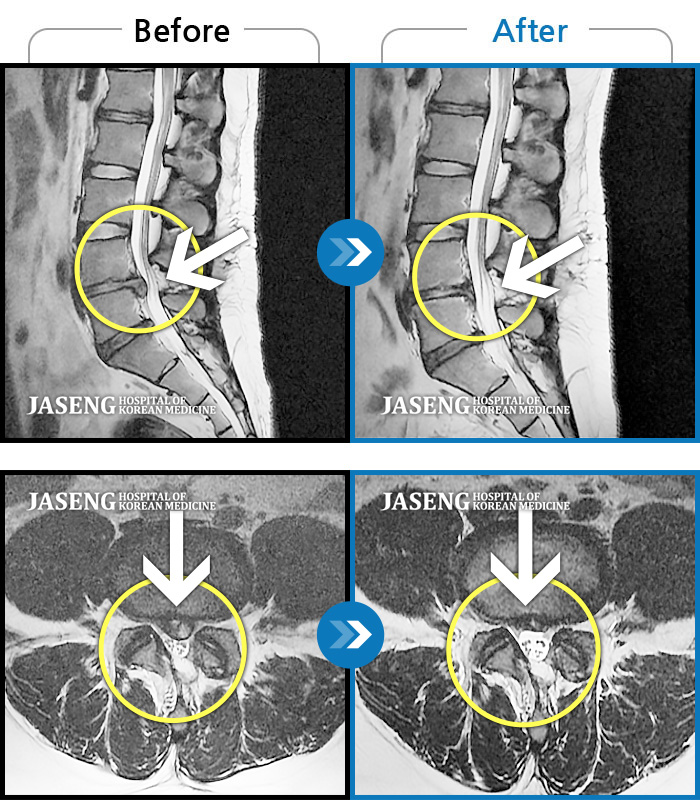

Before

After

환자에게 사전 동의를 받아 동일 조건에서 촬영되었습니다.

개인에 따라 치료 후 부작용이 발생할 수 있으니 의료진과 상담 후 치료를 진행하시기 바랍니다.

좌측 하지 방사통, 보행 불가, 하지 근력 저하

허리 및 좌측 하지 통증